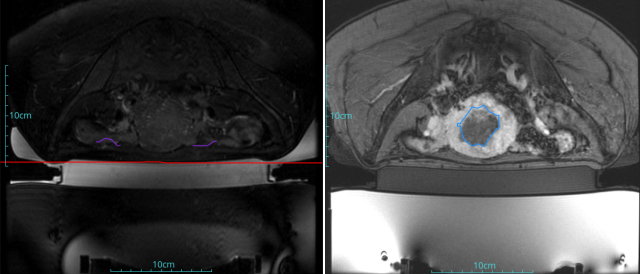

診斷:子宮腺肌癥

病灶尺寸:約為40*37*40mm

ROT深度:病灶的ROT中心距離皮膚45mm

術(shù)后評估:術(shù)后造影增強圖像顯示消融區(qū)域(右側(cè))與病灶區(qū)域(左側(cè))重合度較好,非灌注區(qū)域連續(xù)且一致。

結(jié)論:對該病灶具有非常好的消融效果,治療過程中,溫度上升曲線符合預期,每個被治療的靶點240CEM區(qū)域體積較大、外形飽滿、連續(xù)。病灶消融良好,NPV體積比約80.6%。